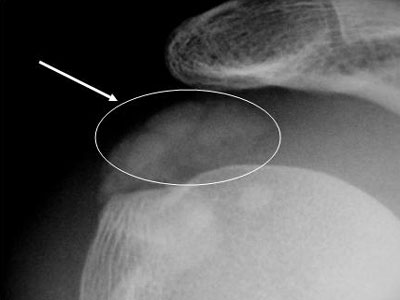

a) Inestabilidad fémoro-rotuliana: freecuente en mujeres jóvenes, deportistas, hiperelásticas y con escasa musculatura cuadricipital. Generalmente se soluciona con tratamiento rehabilitador, pero en casos recidivantes puede ser necesario recurrir a la cirugía, como muestra el caso de lasfotos que se muestran a la derecha, que representan a un deportista que sufrió varias luxaciones de rótula (desplazamiento fuera de su sitio anatómico) que requirió cirugía artroscópica donde se evidenció daño del cartílago de la rótula.

El TAC o escáner sirve para estudiar en profundidad el caso, como este que se muestra a la derecha donde se ve perfectamente la basculación de la rótula con desplazamiento externo, con lo que se encuentra subluxada o fuera del canal troclear.